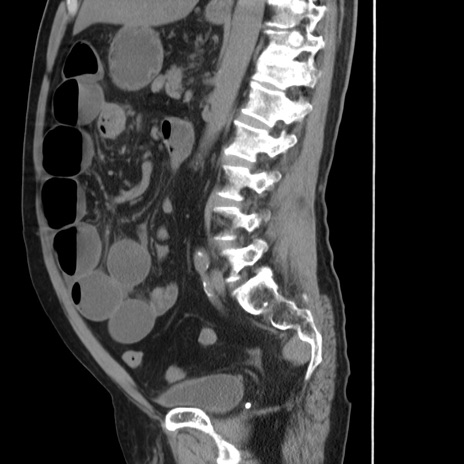

症例20(矢状断像)

【症例】 60歳代男性

【主訴】 腹部膨満、嘔吐

【現病歴】5日前頃より倦怠感を認め食事量減少し4日前の朝嘔吐、食事摂取困難となった。 3日前近医受診し点滴施行され整腸剤などを処方された。 当日他院を受診し、腹部膨満著明、炎症反応の上昇(CRP10.8、WBC11200)あり、紹介受診となる。

【身体所見】 意識JCS1 受け答えがはっきりしないBP 111/57mHg、 P 67bpm、、BT35.2°C、SpO2 97%(RA)、 腹部:膨隆、打診で鼓音あり、全体的に圧痛有り、腸蠕動音(-)、反跳痛ははっきりせず。

【データ】WBC 11400、CRP 14.20